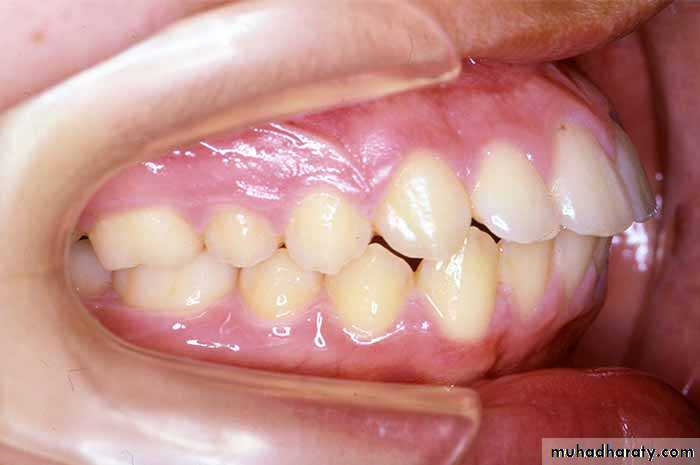

Crowding of teeth:

Defined as a lack of space for all teeth to fit normally with in the jaw.

disharmony in tooth to jaw size relationship.UNIVERSITY OF MOSUL

Classification of crowding:

2- According to severity of crowding:

Mild (1-3 mm)Moderate (3-6 mm)

Severe (more than 6 mm)